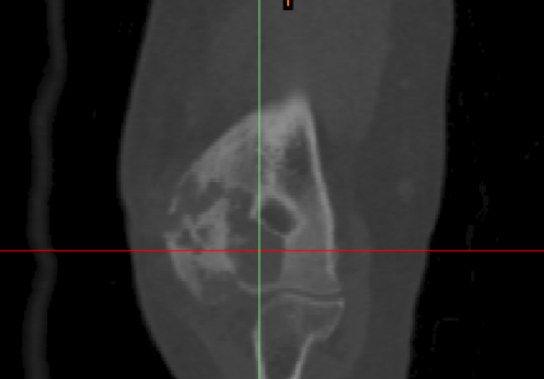

患者樊某,女性,62岁,主诉:15年无明显诱因发现右肘部肿物,伴疼痛酸胀等不适。2016年患者曾于外院行手术切除,术后病理示:血管瘤。术后仍伴疼痛酸胀不适,2017年于上海第六人民医院穿刺活检示:海绵状血管瘤;现患者述右上肢持续性疼痛,较前加重,口服止痛药后可缓解,为进一步诊治,遂来九院门诊。查体诊断为“右肱骨远端骨内血管瘤”。

由于右肘关节受血管瘤侵及,现右肱骨远端骨质严重破坏,拟行右肘部肱骨远端肿瘤切除+右肱骨远端个性化假体重建手术,为精准重建切除后的肱骨远端复杂关节骨缺损,为其定制了3D打印个性化肱骨远端假体。